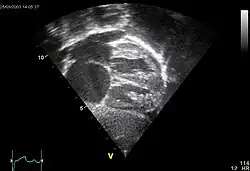

Ultraschall

Goldstandard zur Detektion ist die transösophagale Ultraschalluntersuchung mit einem nicht lungengängigen Kontrastmittel.[21] Manchmal ist bereits mit der Farbdopplerechokardiographie von transthorakal eine ausreichend gute Beurteilung des ASD und des Blutflusses durch den Defekt möglich.